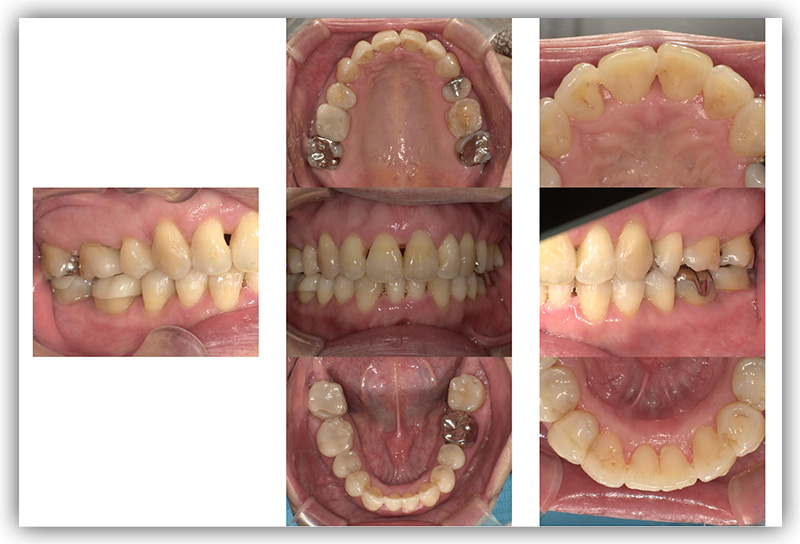

CASE_03

30代女性(インビザライン矯正)

- 患者さん情報(年齢・性別)

- 30代 女性

- 主訴

- 矯正について相談したい。前歯が出ているのがきになる。口が閉じづらい。

- 治療方法

- インビザライン矯正

- 費用

- 88万円

- 治療期間

- 約1年

- その治療によるリスク・副作用

- 歯肉退縮することがある

- 矯正中はしみたり、痛みを伴うことがある

- 患者様の声